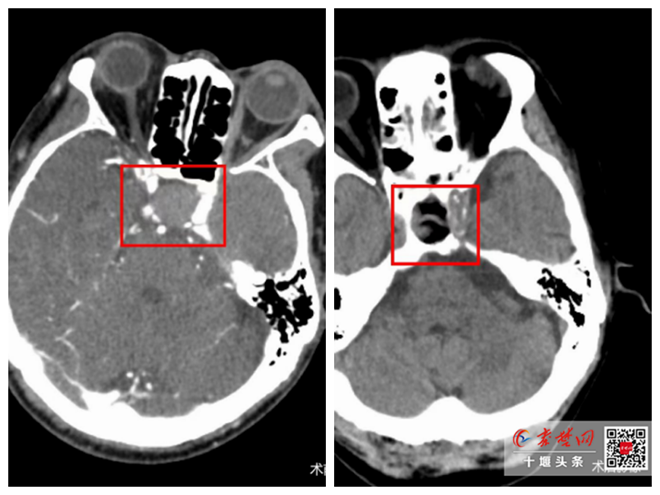

“大血管閉塞性腦梗死”險象環(huán)生!十堰人醫(yī)妙手仁心點(diǎn)亮生命之光

今日房縣網(wǎng)訊?通訊員 馬婷婷 劉瑤 報道:前不久,姜先生因“右側(cè)肢體偏癱合并失語11小時”來到十堰市人民醫(yī)院救治。入院時其右肢體完全癱瘓,神志嗜睡,眼球凝視,急診腦CT檢查排除腦出血,初步診斷為“大血管閉塞性腦梗死”。此病極…